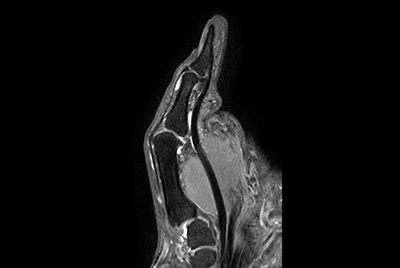

Thumb imaging